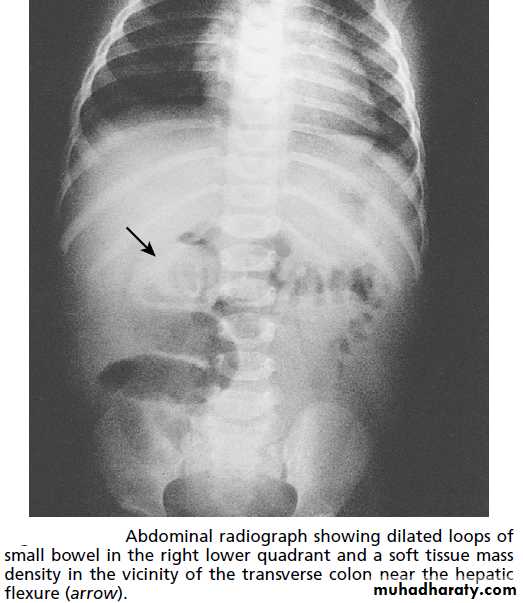

P/R:Dx.1. Plain radiograph

2. US

3. Contrast enema